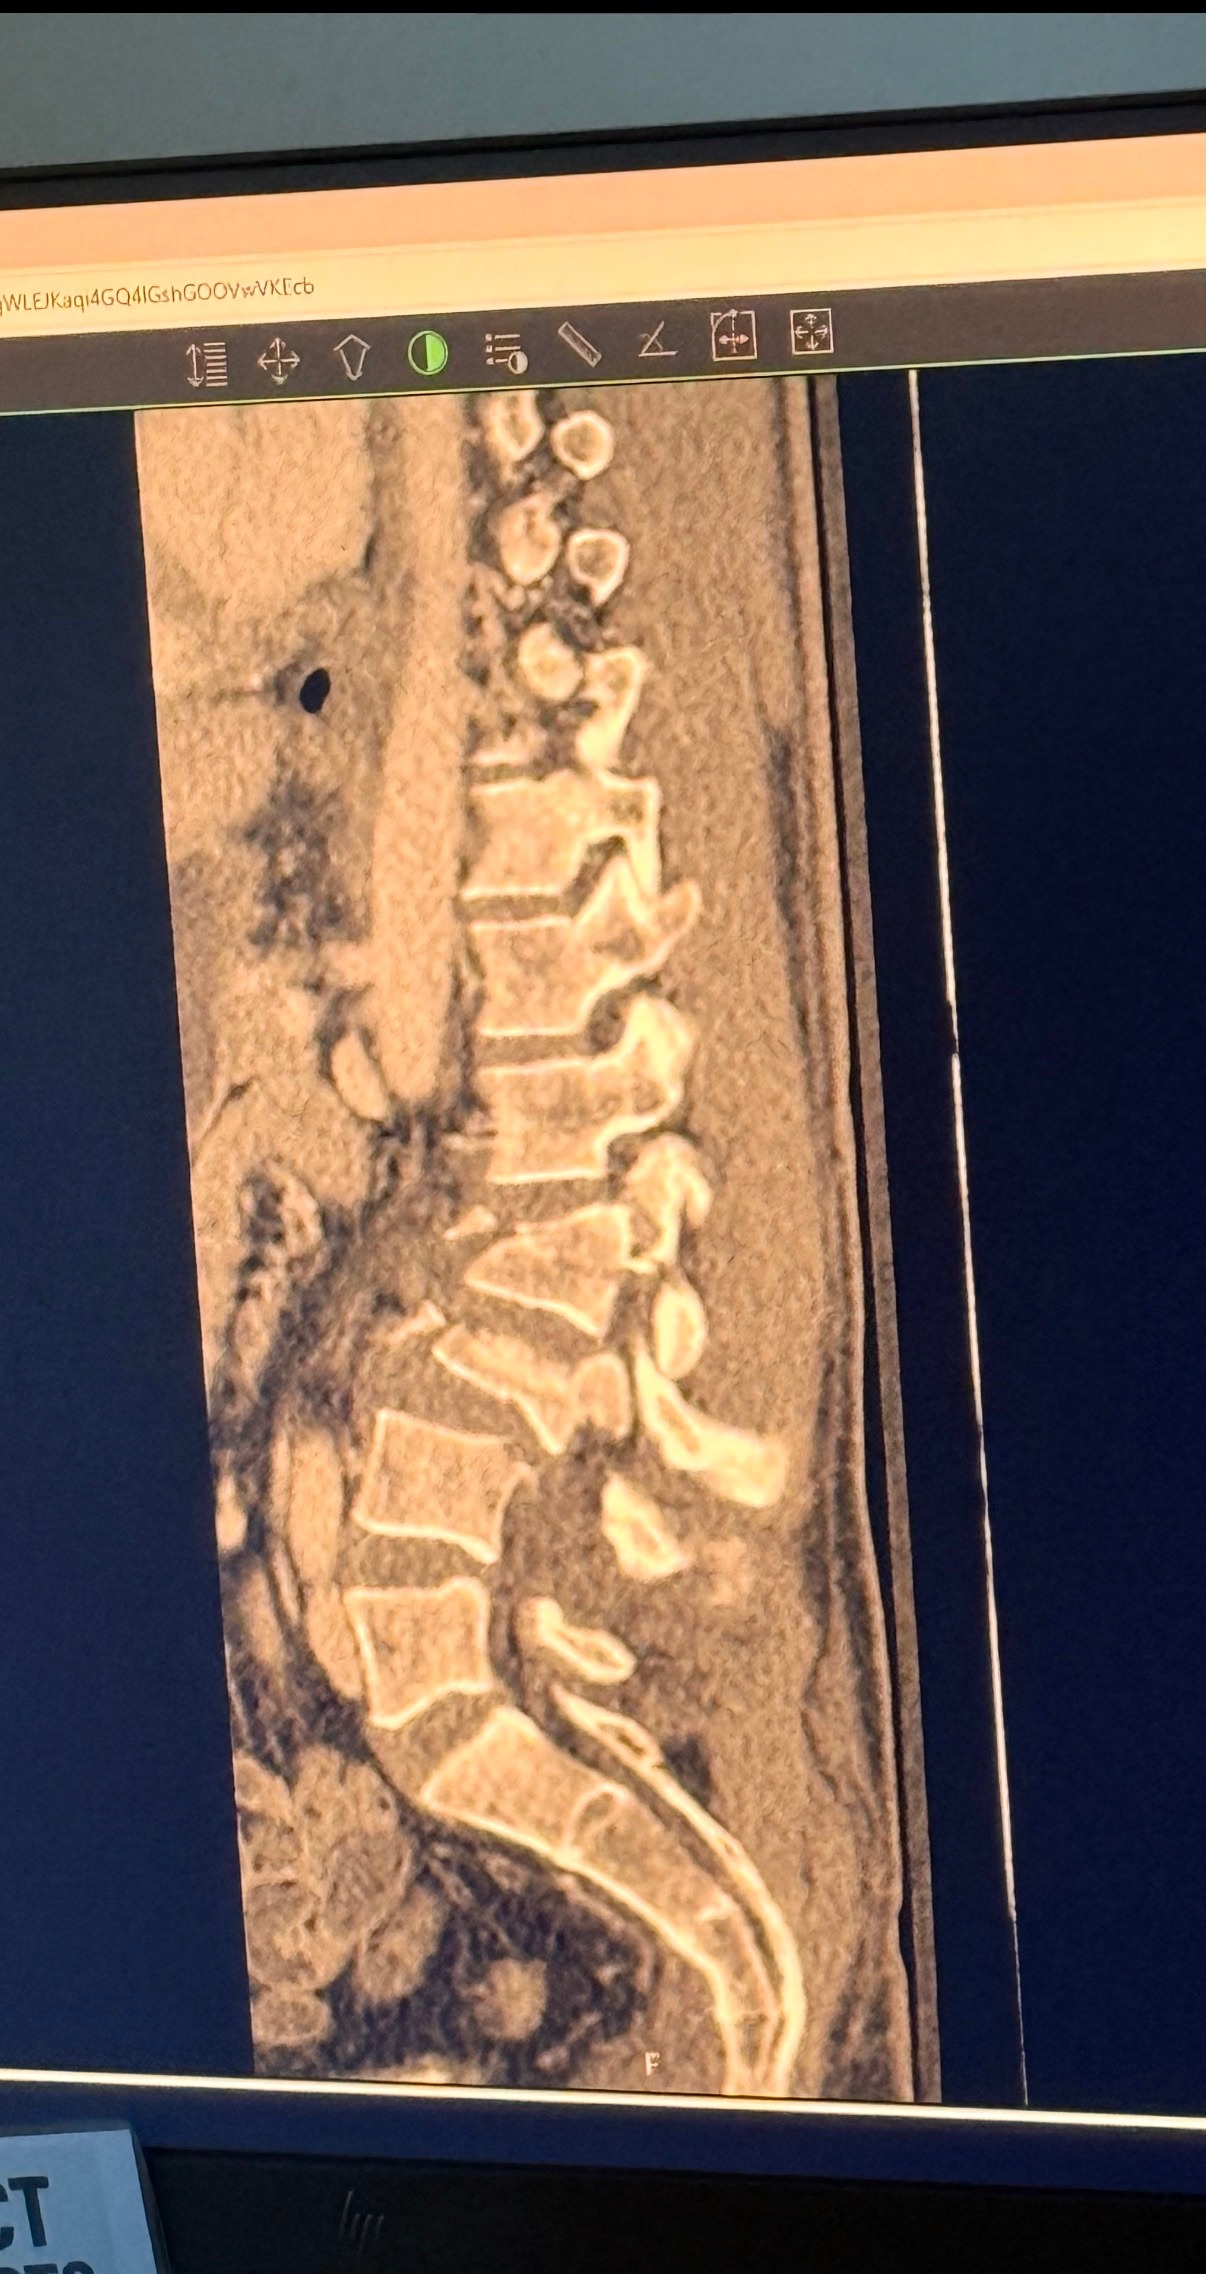

When he reached the hospital, doctors discovered extensive injuries: severe traumatic fractures at L2, L3, L4, and L5, including burst fractures at L2 and L3, pedicle fractures on both sides of L4, and another on the left side of L5. These injuries caused kyphotic deformity, severe spinal stenosis, and major nerve-root compression, which is why he initially lost movement. His spinal cord sac was torn and severely compressed, requiring an extremely delicate emergency surgery to relieve the pressure and repair as much of the damage as possible.

His spine has been straightened and stabilized with screws.

The spinal cord has been repaired and is intact.

All nerves except one were preserved; the surgical team believes the missing one may be sensory, but time will tell as healing continues.